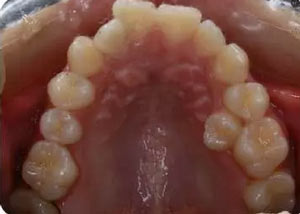

上牙弓:尖圓形,25腭側(cè)完全錯(cuò)位,26前移

下牙弓:卵圓形,下前牙區(qū)擁擠

上牙弓擁擠度9mm;下牙弓擁擠度7mm;

………提示上牙弓較下牙弓狹窄

牙與牙弓:25腭側(cè)完全錯(cuò)位導(dǎo)致26前移,上牙列重度擁擠,下牙列中度擁擠,上牙弓尖圓形,下牙弓卵圓形,第三磨牙牙胚存,18與28牙冠較小且形態(tài)不良

橫向:上下牙弓寬度不匹配,下牙弓寬度較上牙弓大,左側(cè)自第一磨牙開(kāi)始至側(cè)切牙均為反合。上牙列中線左偏,下牙列中線右偏。